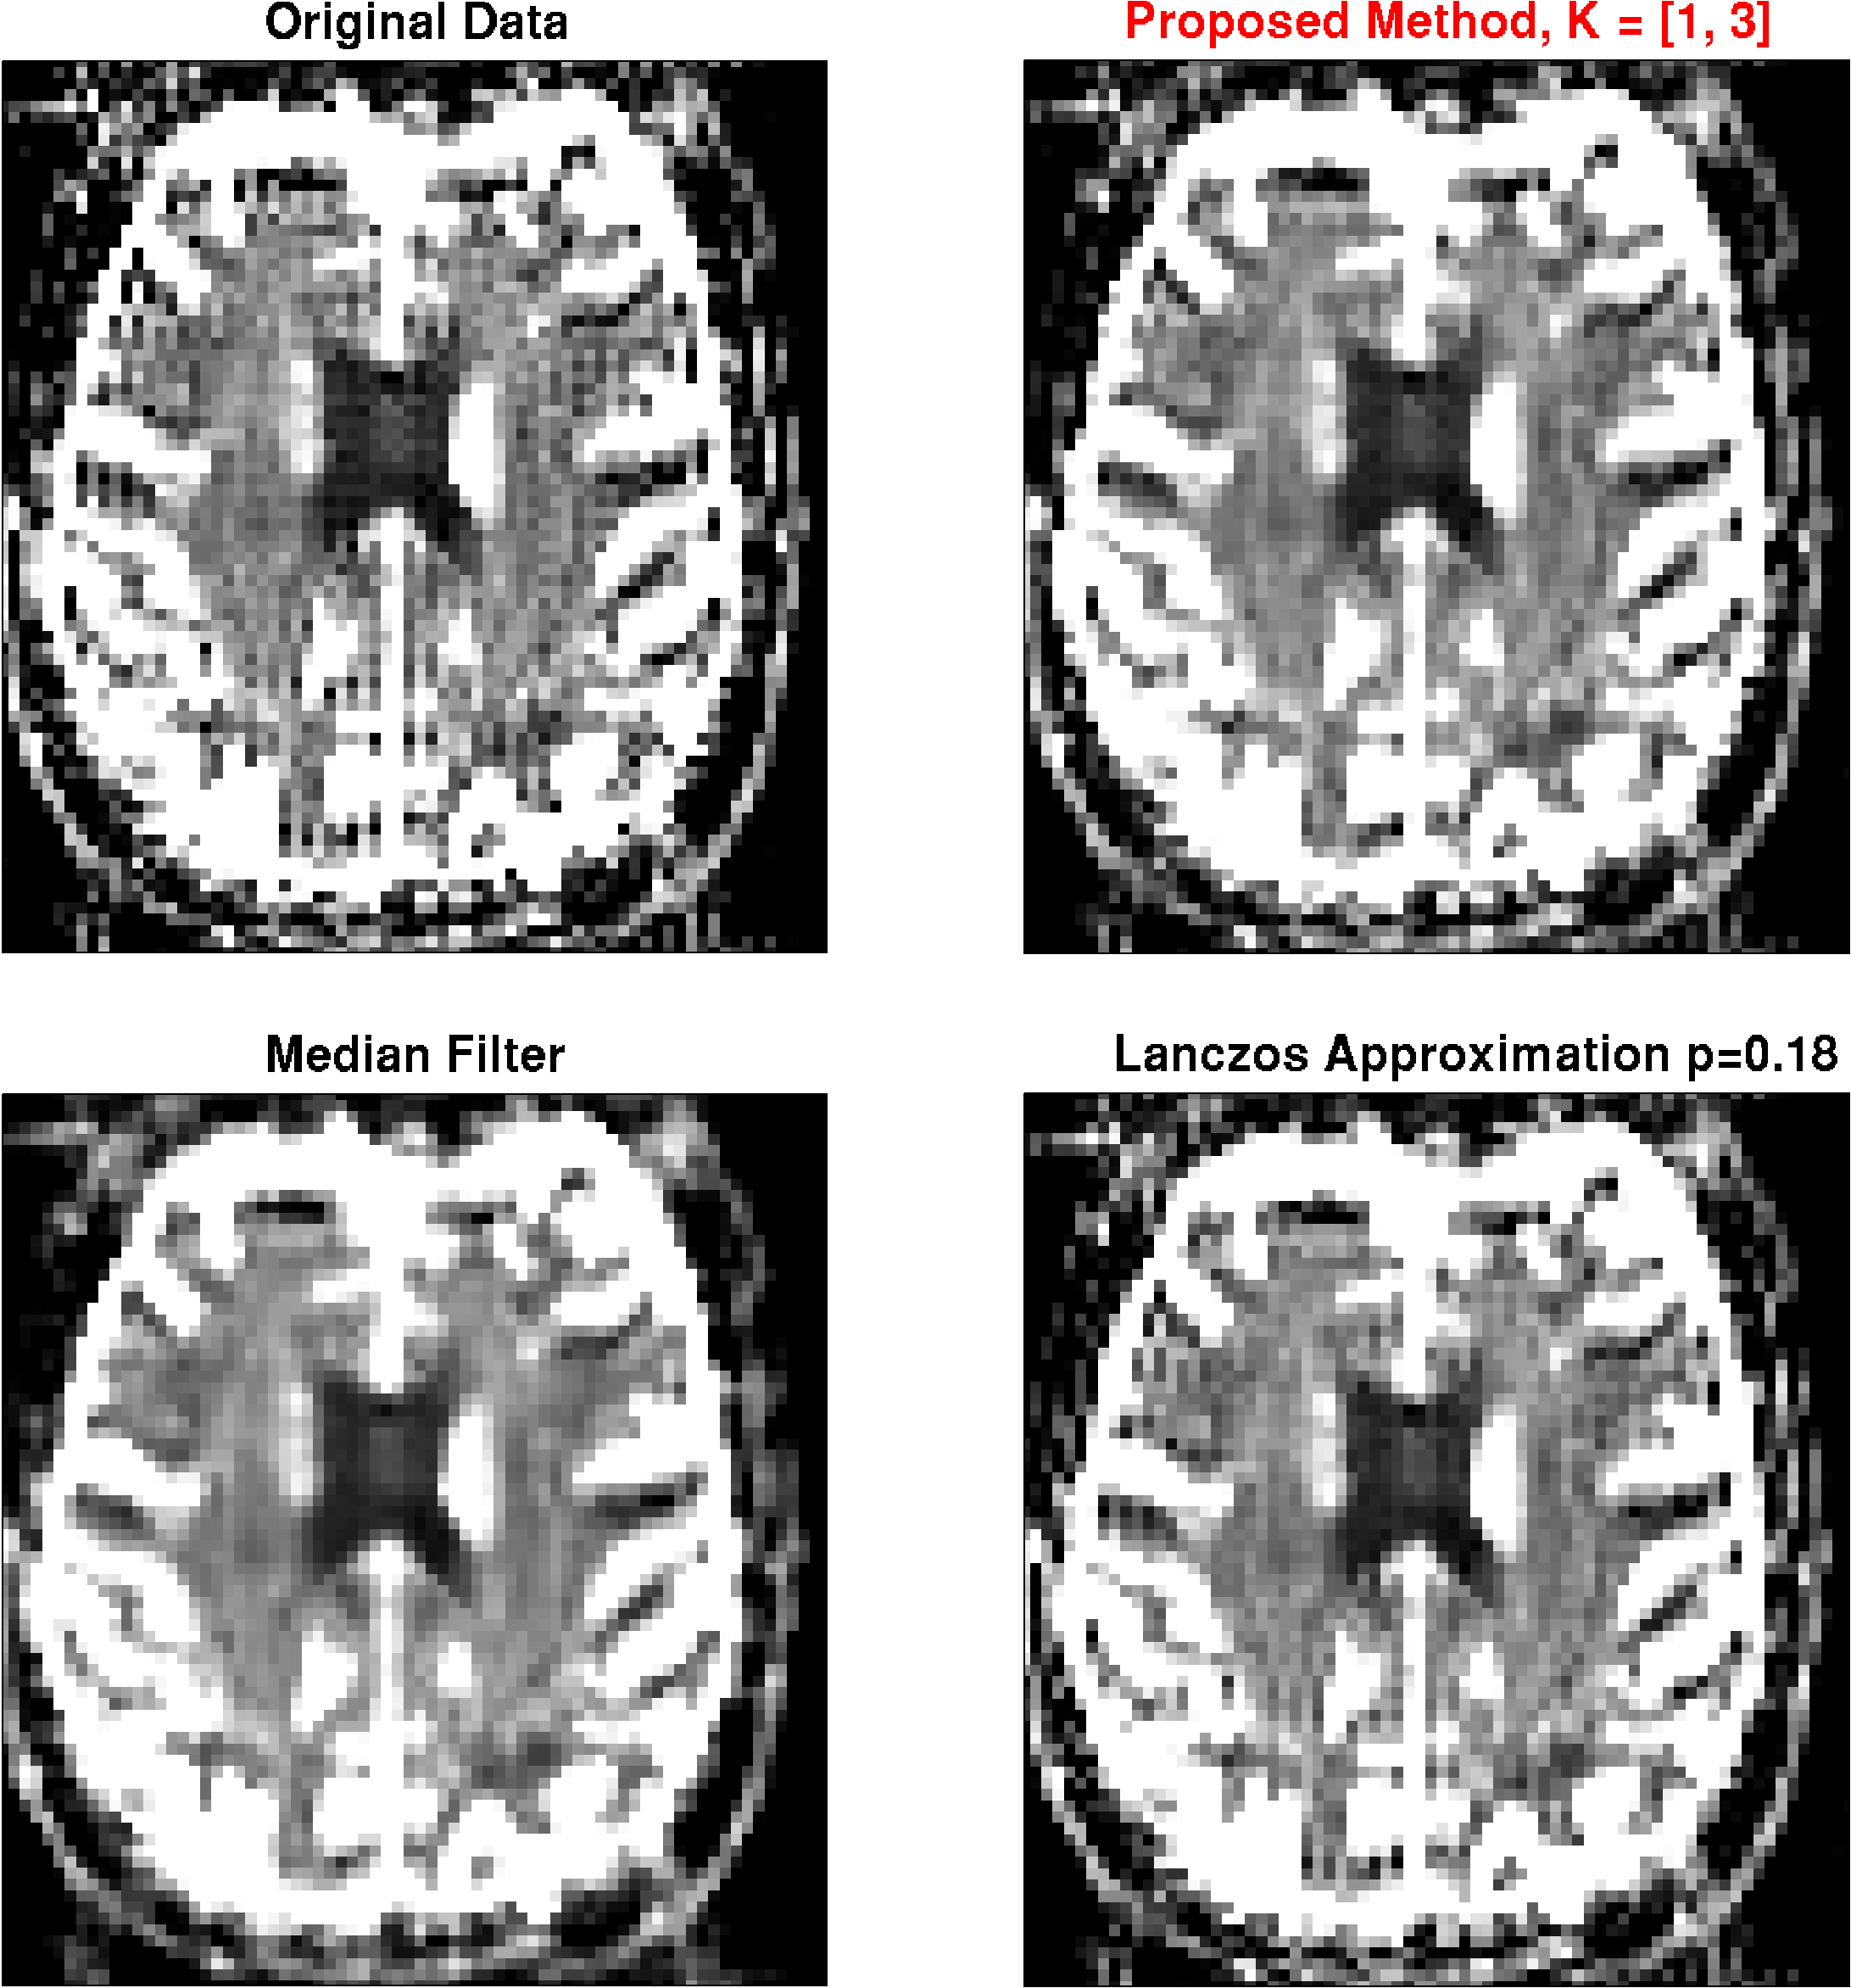

The results of the phantom simulations are shown in Fig. 4. We show results using the median filter, the Lanczos approximation with , results obtained with the proposed method using different parameters, and results using the Lanczos approximation with filter parameters adapted to yield an equal noise correlation as the proposed method.

Obviously, the median filter preserves the edges better than the Lanczos-approximation with , at a smaller increase in the average smoothing, indicated by the smaller increase in noise correlation. However, it shows a stronger residual of the artifact, and fine image details like small, peak-like structures are destroyed. With the proposed method, on the other hand, the artifact can effectively be removed with minimal smoothing of edges. The method is rather robust against the choice of the kernel parameter. A larger neighborhood results in less smoothing, but comes at the price of slightly reduced artifact removal. A kernel size of seems to be a appropriate compromise between artifact removal and noise correlation. This setting is used for the application to the MRI images.

These findings are basically the same for the phantom constructed from the -weighted image in Fig. 5. Also here, the artifact can most effectively be removed using the proposed method, while preserving fine image details.